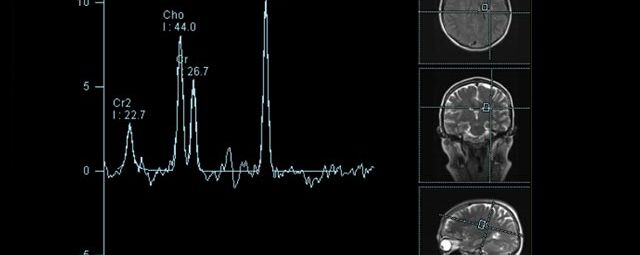

Spezialtechniken der Magnetresonanz

• MR-Spektroskopie

Diese Untersuchung führen wir ausschließlich an unserem Standort in Leipzig am Diakonissenkrankenhaus durch. Bitte nehmen Sie zur Vereinbarung eines Termins telefonischen Kontakt mit uns auf: 0341 3937-3000 oder schreiben Sie uns eine E-Mail an: